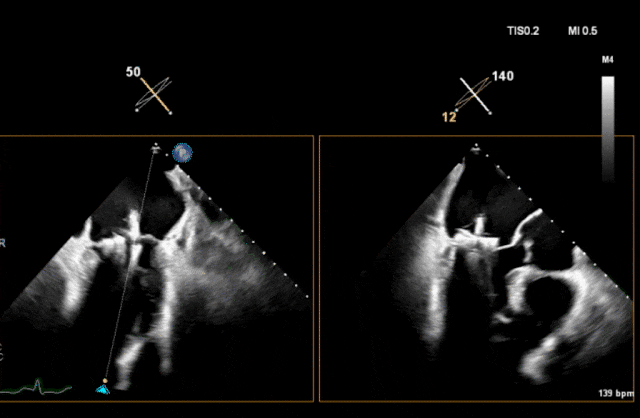

术前瓣叶

图片